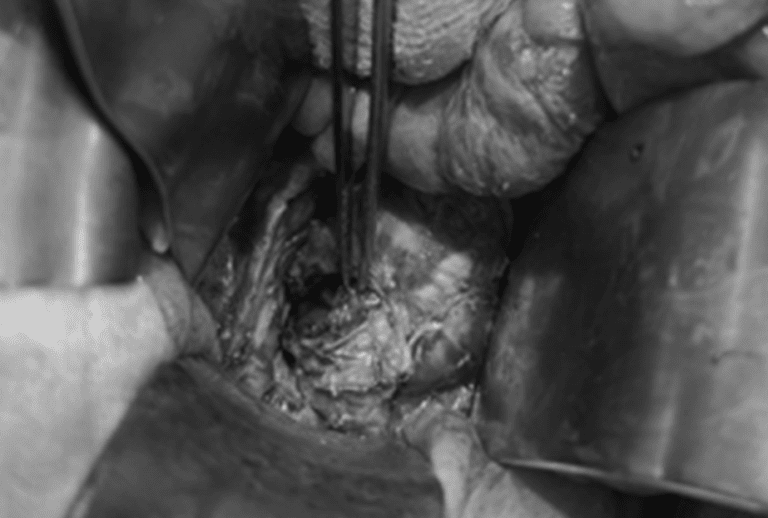

Quá trình phẫu thuật ghi nhận tổn thương vỡ trực tràng 1/3 dưới gây áp xe khoang sau phúc mạc. Kíp phẫu thuật đã tiến hành khâu chỗ vỡ trực tràng, đồng thời dẫn lưu rộng rãi khoang sau phúc mạc và làm hậu môn nhân tạo đoạn đại tràng Sigma. Sau 14 ngày, bệnh nhân xuất viện và đã ăn uống, sinh hoạt bình thường, tuy nhiên bệnh nhân sẽ phải chịu một cuộc phẫu thuật nữa sau vài tháng để đóng lại hậu môn nhân tạo.